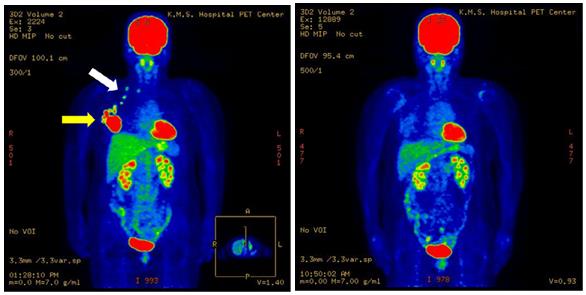

(圖2)57歲女性,右乳癌進展期。左圖為治療前PET-CT圖像。腫瘤病灶(黃色箭頭),腋窩淋巴結轉移,鎖骨淋巴結轉移(白色箭頭)。右圖為治療后5年8個月的圖像,未復發。